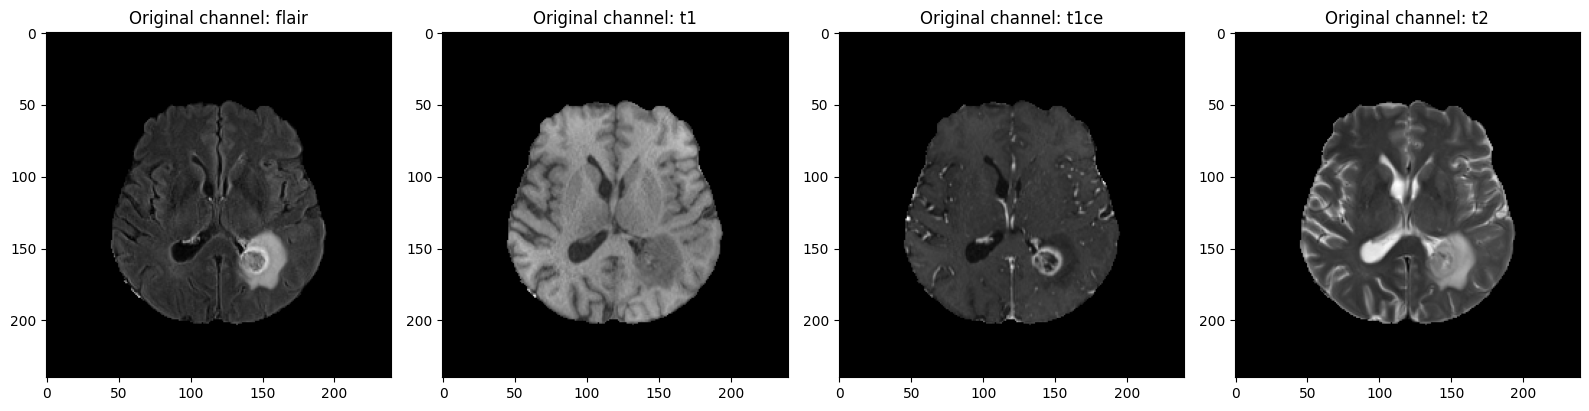

Let's begin by examining the original input slices from the MRI scan. The input contains four channels corresponding to different MRI modalities: - FLAIR - T1 - T1CE (T1 with contrast enhancement) - T2 We display the same slice number across all modalities for comparison.

slice_map = {0: "flair", 1: "t1", 2: "t1ce", 3: "t2"}

slice_num = 75

plt.figure(figsize=(16, 4))

for i in range(orig_image.shape[-1]):

plt.subplot(1, 4, i + 1)

plt.title(f"Original channel: {slice_map[i]}")

plt.imshow(orig_image[slice_num, :, :, i], cmap="gray")

plt.tight_layout()

plt.show()